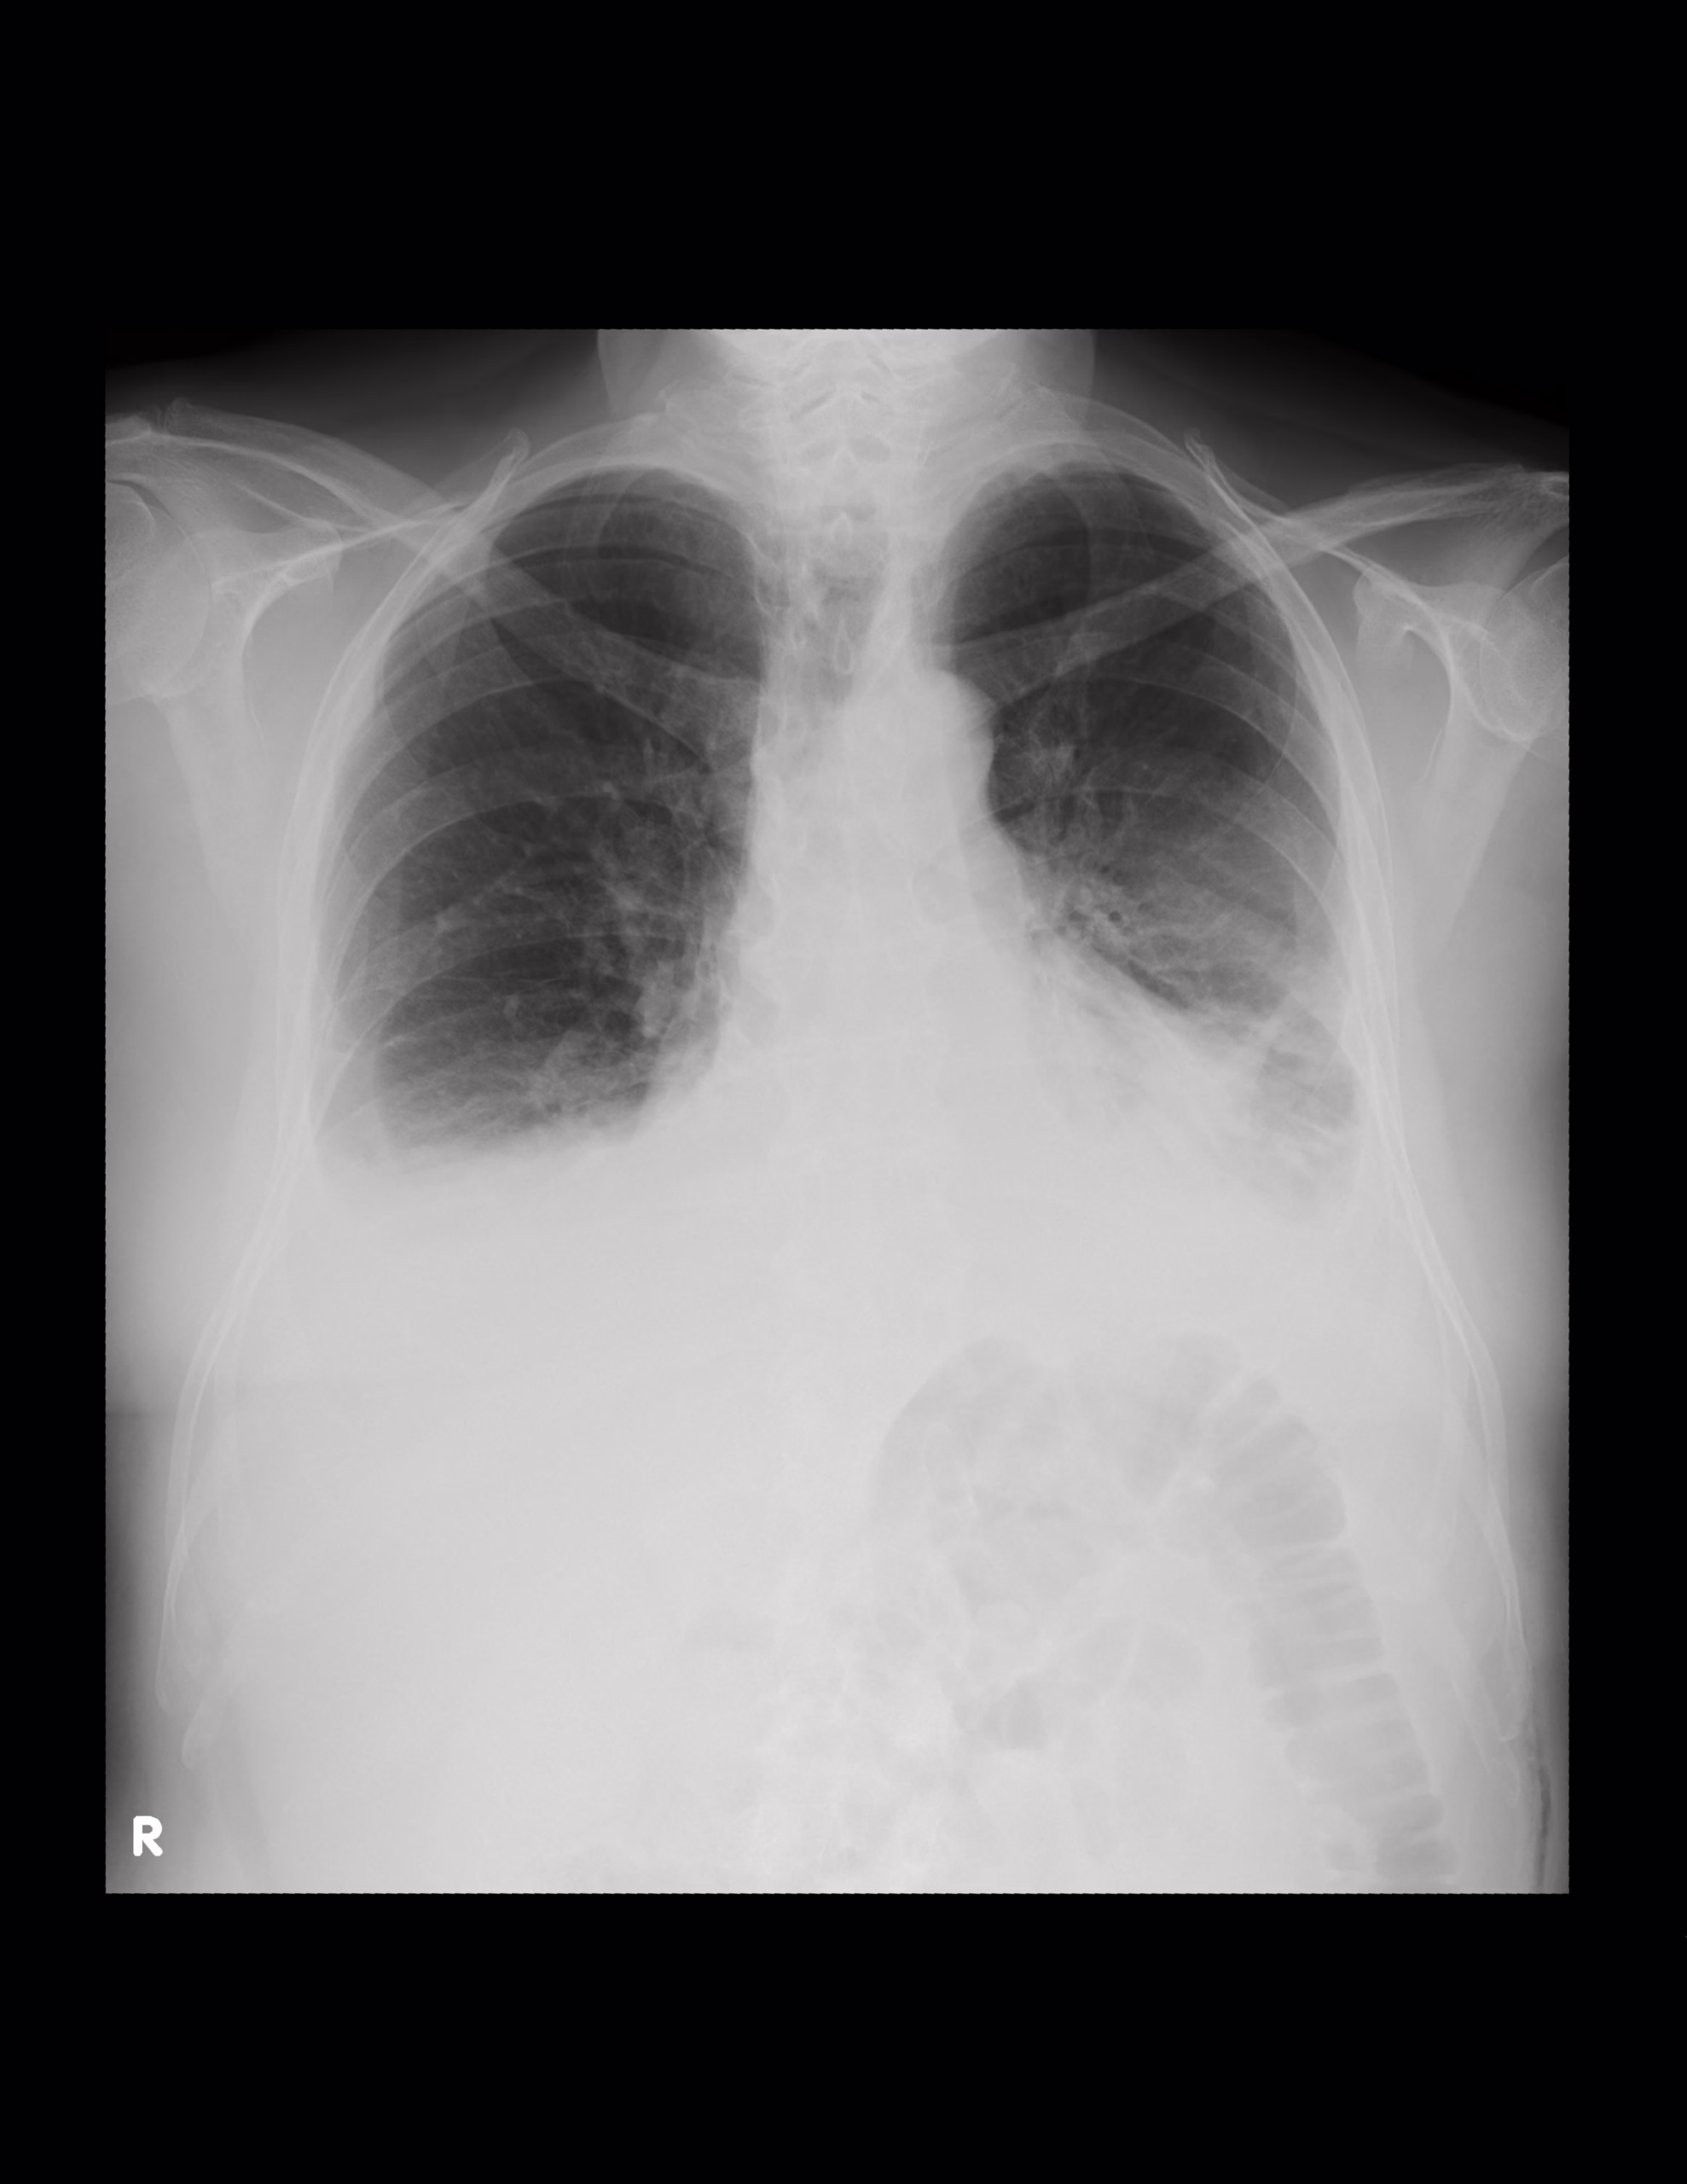

PA DE TORAX (TELE DE TORAX)

LA PROYECCION RADIOLOGICA OBTENIDA NOS MUESTRA LOS SIGUIENTES HALLAZGOS:

-Tejidos blandos, simétricos, con adecuada densidad, sin evidencia alteraciones.

-Estructuras óseas, sin evidencia de lesiones líticas, blásticas o perdida de la contigüidad. Existen osteofitos marginales.

-Vía aérea permeable, con leve desviación hacia la derecha a expensas de Botón aórtico. Botón aórtico con calcificaciones.

-Mediastino, conservando sus diámetros.

-Corazón, central, con índice cardiotorácico de 0.55

-Hilios pulmonares, derecho observado parcialmente. Izquierdo sin alteraciones.

-Trama bronco-vascular, de lo observado con adecuado trayecto, densidad y calibre.

-Campos pulmonares, ambos con presencia de atelectasias basales

-Recesos costofrénicos y cardiofrénicos ocupados.

EN EL PRESENTE ESTUDIO RADIOGRÁFICO, EXISTEN ATELECTASIAS BIBASÁLESES CON DERRAMÉ PLEURAL ASOCIADO.

CARDIOMEGALIA GRADO II.

CAMBIOS OSTEODEGENERATIVOS Y ATEROESCLEROSIS.